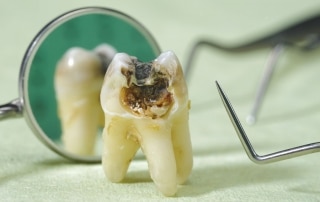

Karies

Karies je najbolj razširjena bolezen današnjega časa in najpogostejši razlog obiskovanja zobozdravnikov. V Sloveniji...